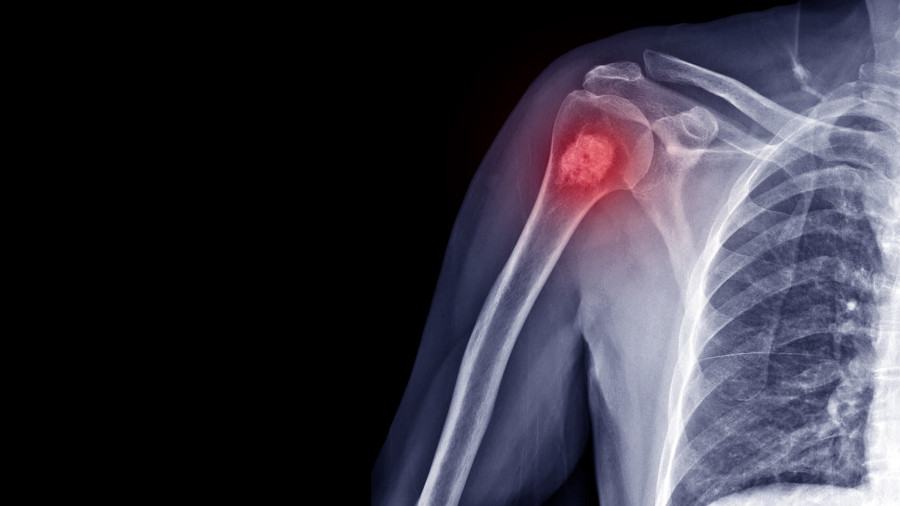

За да се постави диагноза остеосарком, внимателно се оценяват оплакванията и клиничните находки при пациента. Най-честите симптоми включват болка в костите, подуване и ограничение в движението. Болка, която се засилва особено нощем, както и дискомфорт при физическа активност, са характерни признаци на остеосарком. За потвърждение на диагнозата се използват съвременни методи за образна диагностика. Рентгенови снимки, ядрено-магнитен резонанс (ЯМР) и компютърна томография (КТ) помагат за установяване на разпространението на тумора в костта и околните тъкани. Окончателната диагноза се поставя чрез биопсия. В Acıbadem Healthcare Group този процес се извършва от опитни патолози, за да се гарантира максимално точен и бърз резултат.